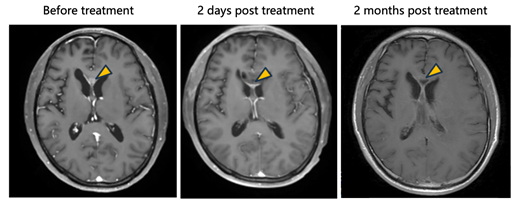

· In one patient treated with tumor resection followed by intracavitary injection of NXL-004, postoperative imaging demonstrated progressive tumor reduction leading to complete radiographic disappearance, achieving a complete response (CR).